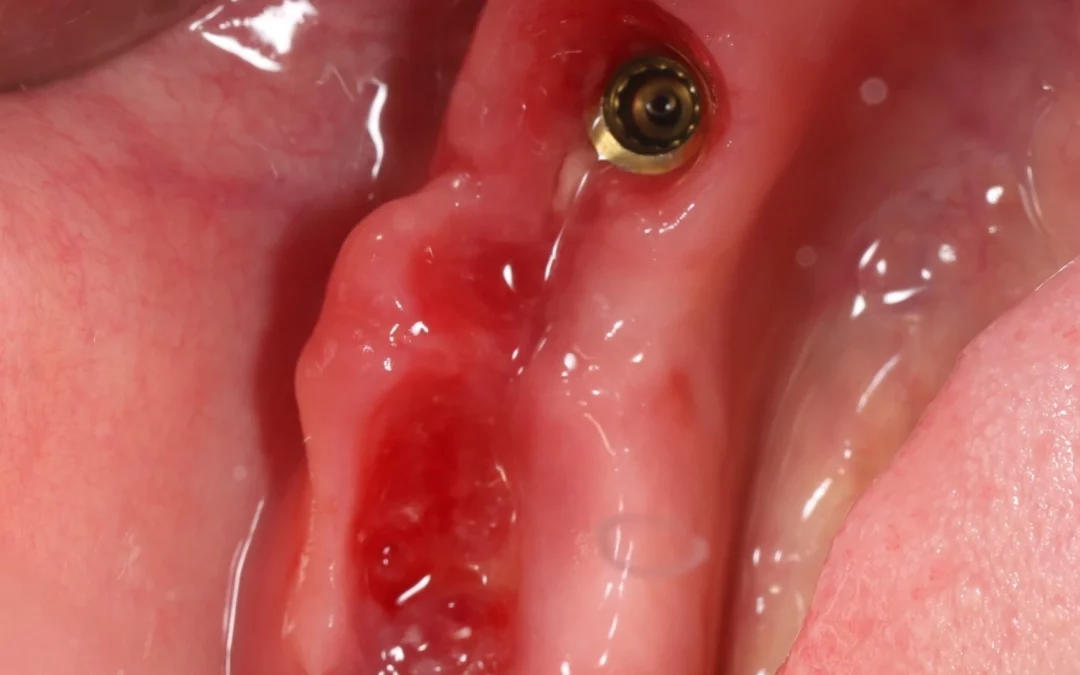

Имплантация MIS C1 по шаблону Одномоментная имплантация у нас всегда заканчивается фиксацией временной цирконевой коронки, или индивидуального формирователя десны так же из Zr, но если ситуация экстренная и...